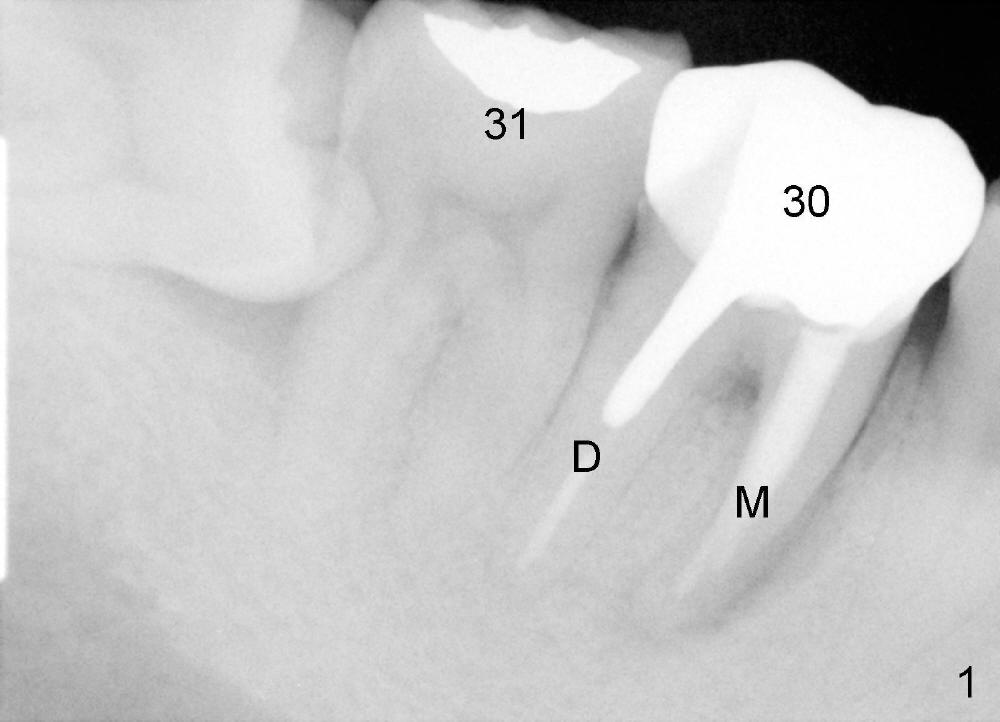

A 40-year-old man presents to clinic with chief complaint of pain in the lower right 1st molar. Exam reveals a fistula in the mesiobuccal area. PA shows a large radiolucency associated with the mesial root. Where should an immediate implant be placed?